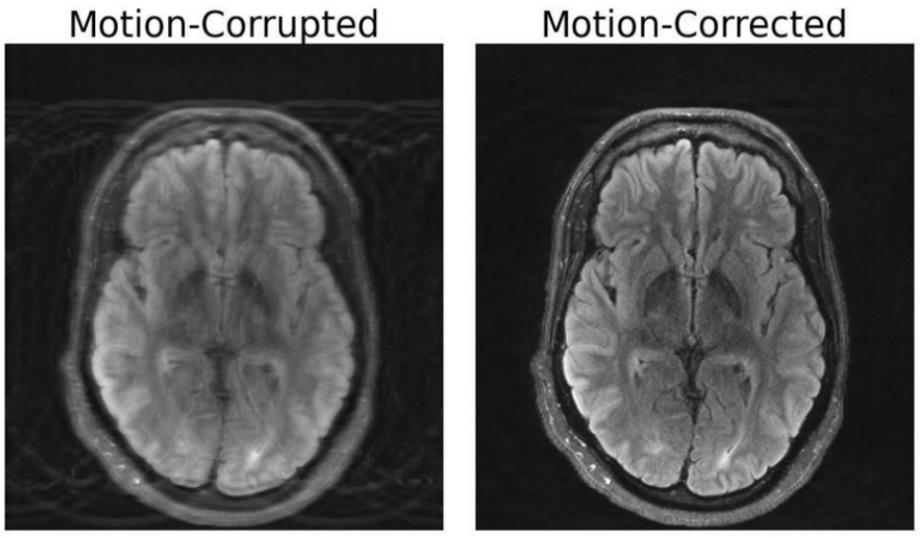

Corrección de movimiento en las imágenes de resonancia magnética

Investigadores del MIT pueden haber desarrollado un modelo de aprendizaje profundo capaz de corregir el movimiento en la resonancia magnética del cerebro.